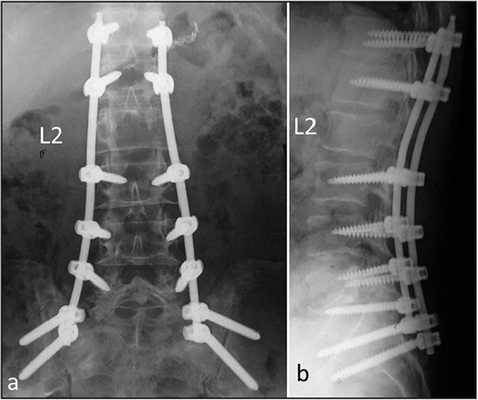

Стабилизационная система на рентгене.

В большинстве случаев проблемный сегмент стабилизируют с помощью металлоконструкций, чаще представленных транспедикулярными системами и пластинами с винтами из высокотехнологичных сплавов металла. В хирургии такая техника называется инструментацией позвоночника. Кроме металлоконструкций, для стабилизации также могут быть применены полимерные устройства, сделанные, например, из углеводородного волокна или резорбирующегося высокомолекулярного биополимера. К отдельной разновидности стабилизирующих вмешательств, которые не причисляют к инструментации, относят установку кейджей имплантатов межпозвоночных дисков.

Жесткие, или неподвижные металлоконструкции подразумевают закрепление позвонков в постоянном фиксированном положении. Устанавливаются они из заднего доступа (со стороны спины) под контролем КТ и рентген-аппаратуры. Крепятся к позвонкам резьбовыми винтами, которые погружают в костные тела на глубину до 80%. Рекомендуют ставить подобного плана системы сугубо в безальтернативных случаях, если ни один другой вид лечения не сможет решить проблему с поврежденным отделом позвоночника.

- Система создана для универсальной фиксации торакального и люмбального отделов позвоночника. Представляет собой «умную» комбинацию из титановых стержней и винтов, способствующих быстрому и качественному формированию артродеза.

- Характеризуется изначально высокими стабилизирующими свойствами, отличными критериями прочности и устойчивости к большим нагрузкам. Более того, нагрузки, которые оказывают воздействие на конструкцию, рационально распределяются между всеми ее структурообразующими элементами и стабилизированными позвонками.

- Главной особенностью изделия является редукционный 3-D инструментарий, фиксирующийся на винтах. Инструмент дает возможность выполнять сопоставление и/или редукцию в любом порядке очередности. К тому же, эта модель ТПФ не требует установки поперечных коннекторов, а вариабельность диапазона угла при введении винта в пластину составляет 45 градусов.

- Установка конструкции предполагает малоинвазивное вмешательство, а именно: минимальный доступ с достаточно четким обзором, отсутствие больших кровопотерь, аккуратность по отношению к позвоночным и околопозвоночным тканям, высокую безопасность для спинномозговых корешков и сосудистых образований.

- Грамотно спроектированное приспособление позволяет заметно сократить время оперативного сеанса, снизить осложнения и достичь хороших результатов уже в раннем послеоперационном периоде. После установки, как правило, в ношении корсета нет необходимости.

Стабилизация поясничного отдела.